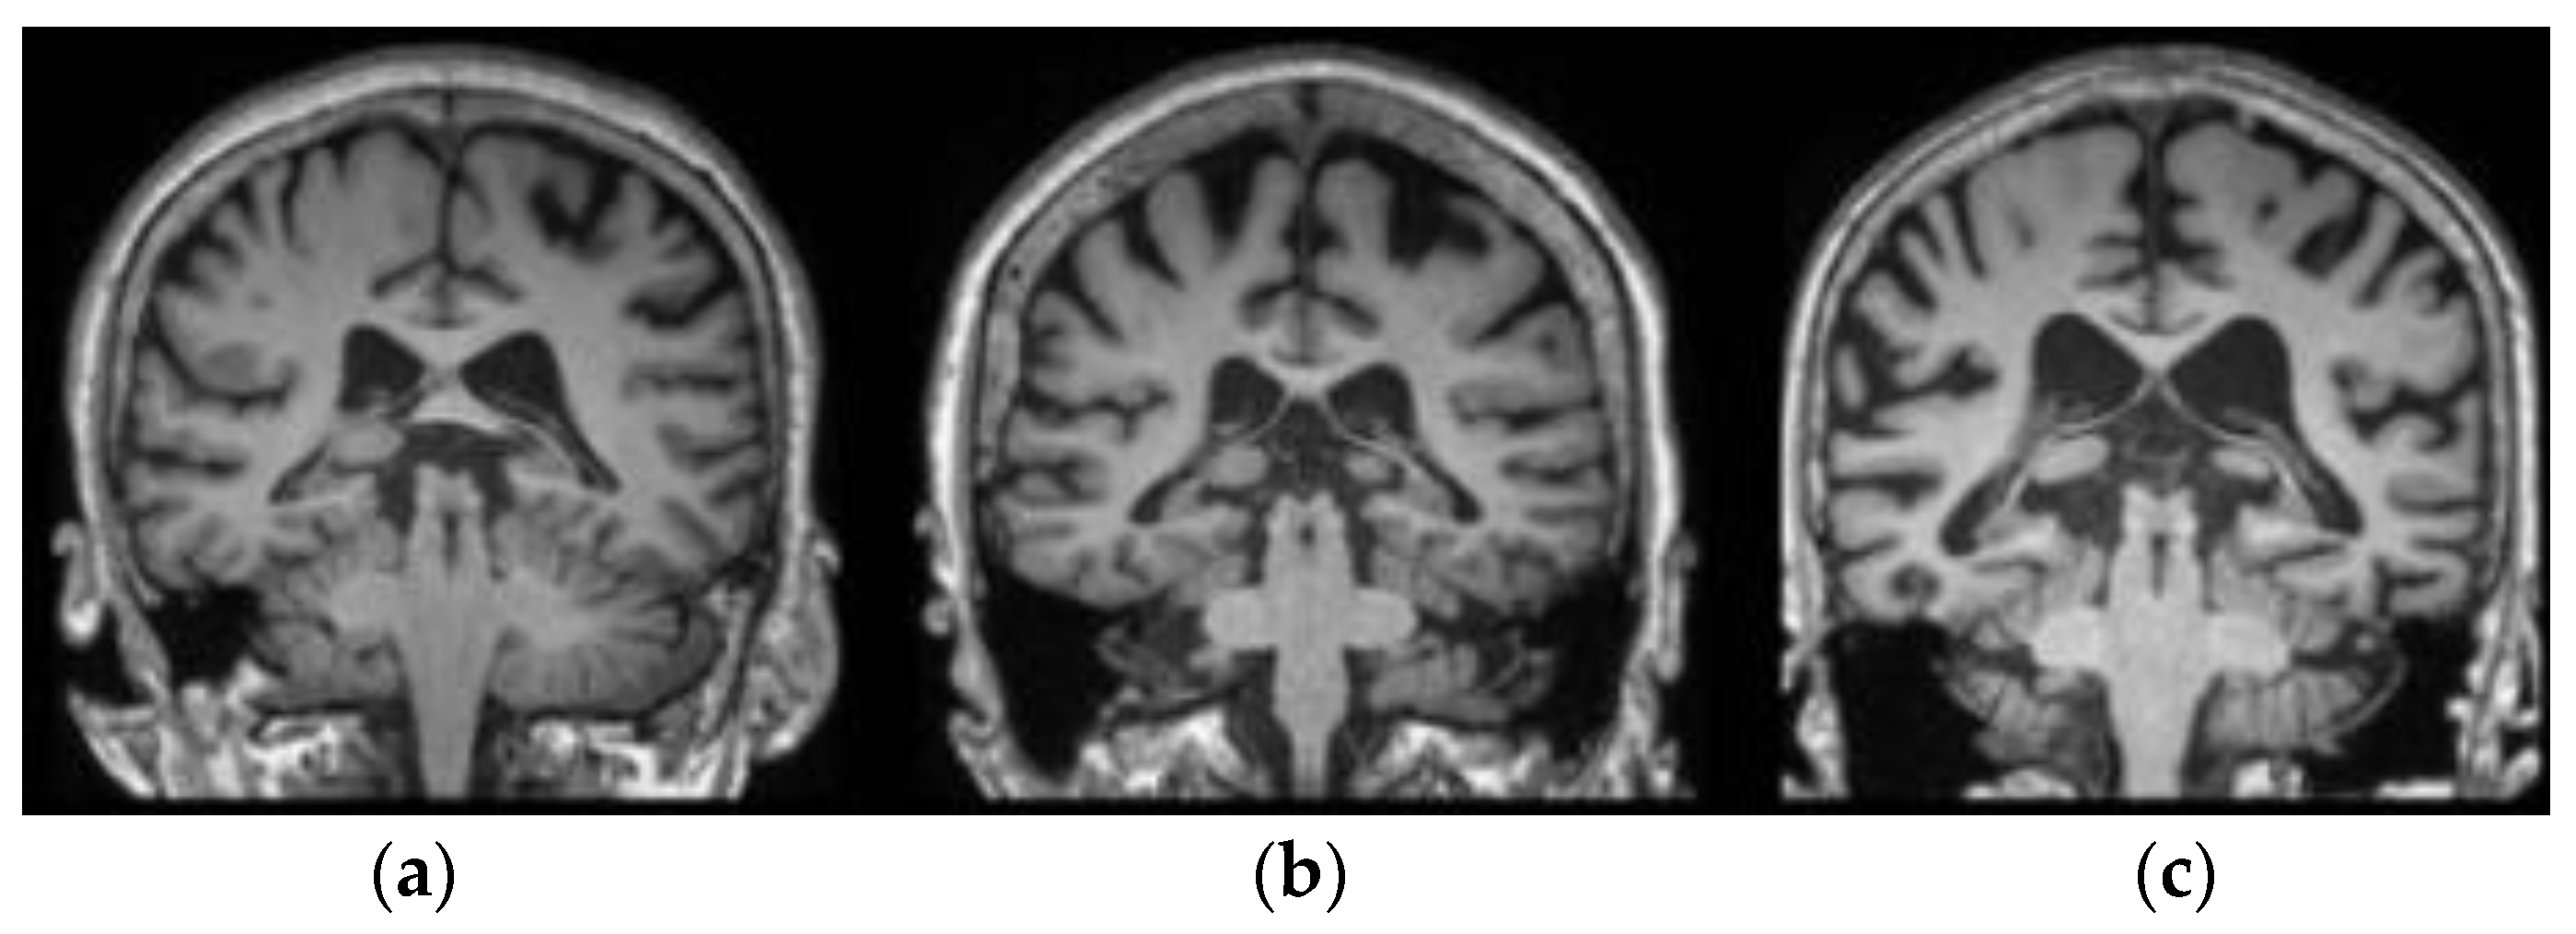

where S = c v 1 c v 2 255 , and   m = ( S p t 1 S p t 2 ) ^ 2 . The parameters S and m represent the colour similarity and distance between the seed points   S p t 1   a n d   S p t 2 , respectively. When the computed value of D i is maximum, the two pixels are very similar. As an outcome, a greater number of super pixels are segmented from the sMRI images, and the resultant image is presented in Figure 3. The hippocampus portions are marked in red colour in the respective sMRIs.

Figure 3. Segmented hippocampus portion from the sMRIs: (a) ADNI dataset, (b) real-time dataset, and (c) AIBL dataset.